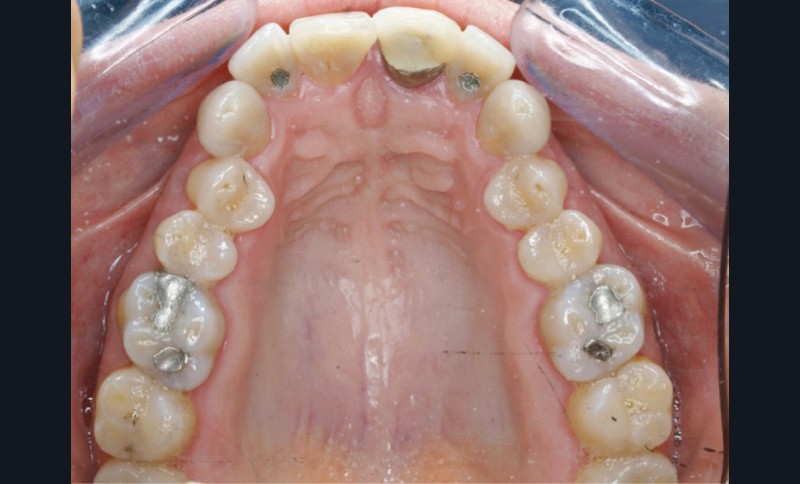

En 2008, la patiente, âgée de 34 ans, se présente pour le traitement de ses « dents mal placées, et de l’écart entre les dents du haut et du bas » (fig. 1). Elle a déjà bénéficié d’un traitement adolescent par plaque amovible maxillaire.

Au niveau exobuccal, la patiente présente un visage convexe avec un étage inférieur de la face augmenté et une absence de contact bilabial au repos traduisant un contexte dysfonctionnel. Le sourire est gingival et étroit.

L’analyse endobuccale et l’étude céphalométrique (fig. 2, tableau 1) confirment le diagnostic de classe II squelettique hyperdivergente avec une classe II molaire et canine bilatérale, associée à un encombrement, à une dysharmonie du sens transversal par endoalvéolie maxillaire, et une béance antérieure par infra-alvéolie incisive maxillaire dans un contexte dysfonctionnel de la musculature péri-labiale et mentonnière.